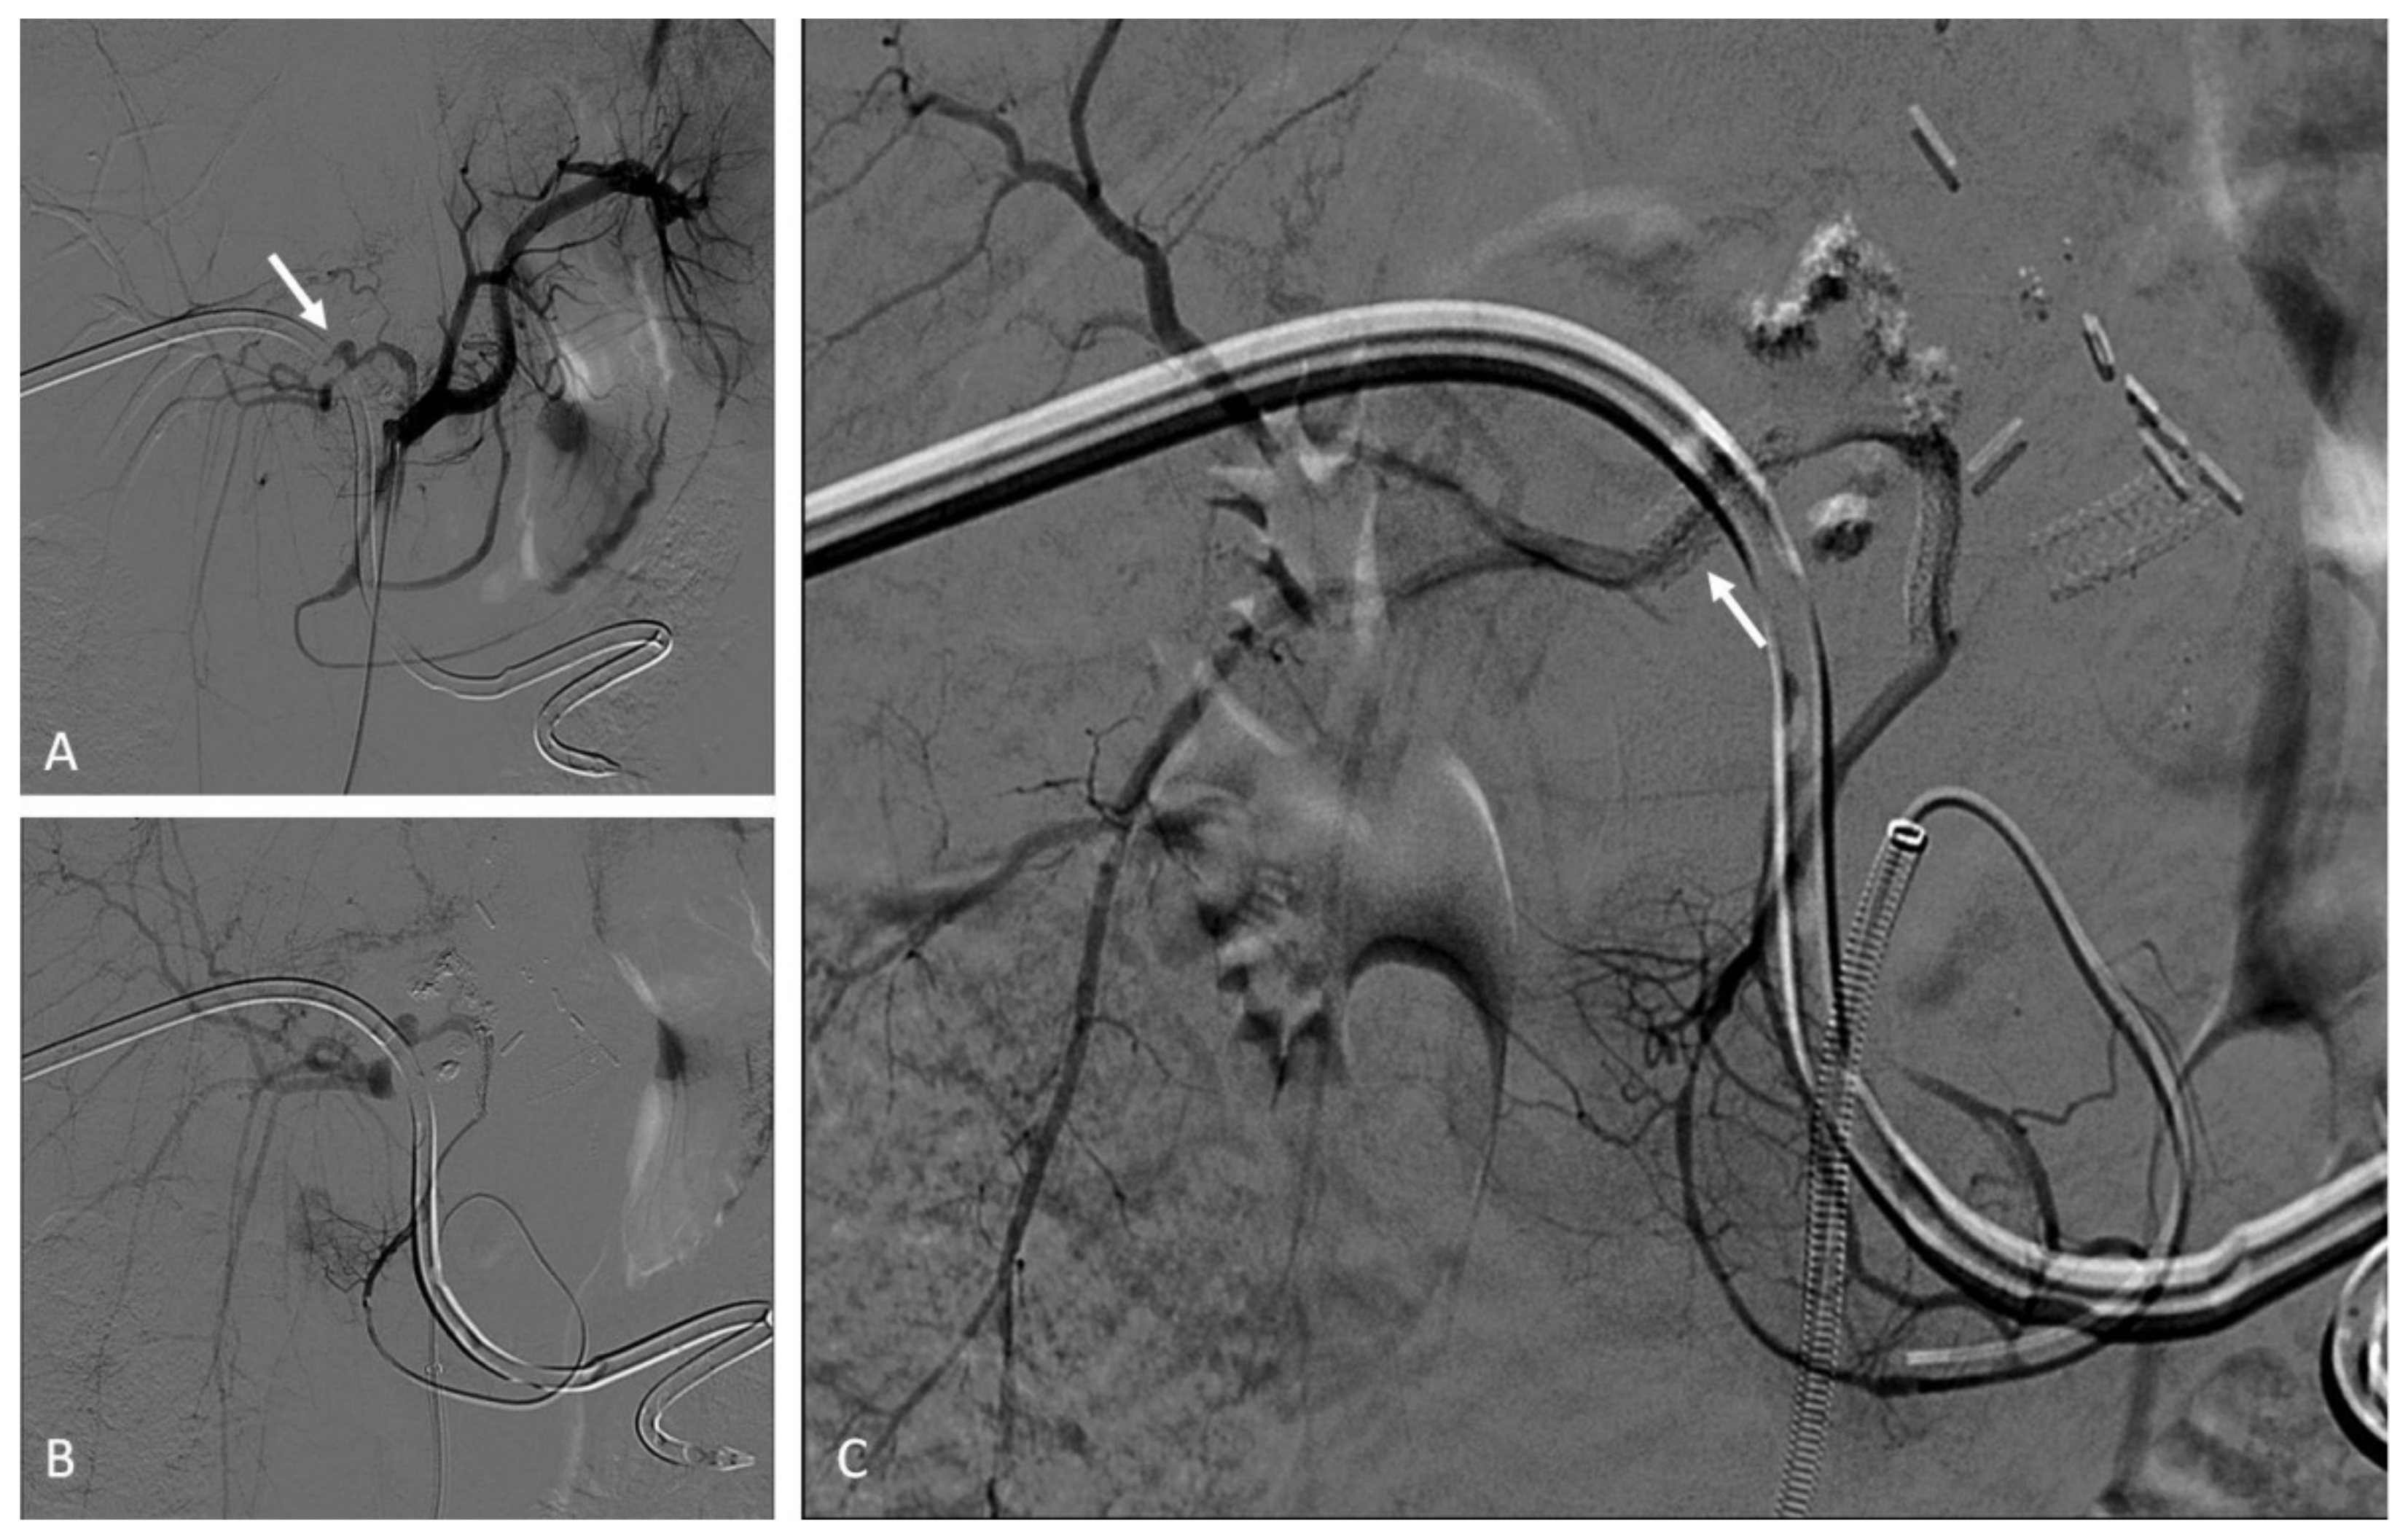

12. Porto-Systemic Shunts

12.1. Indications

12.2. Techniques

12.3. Clinical Outcomes